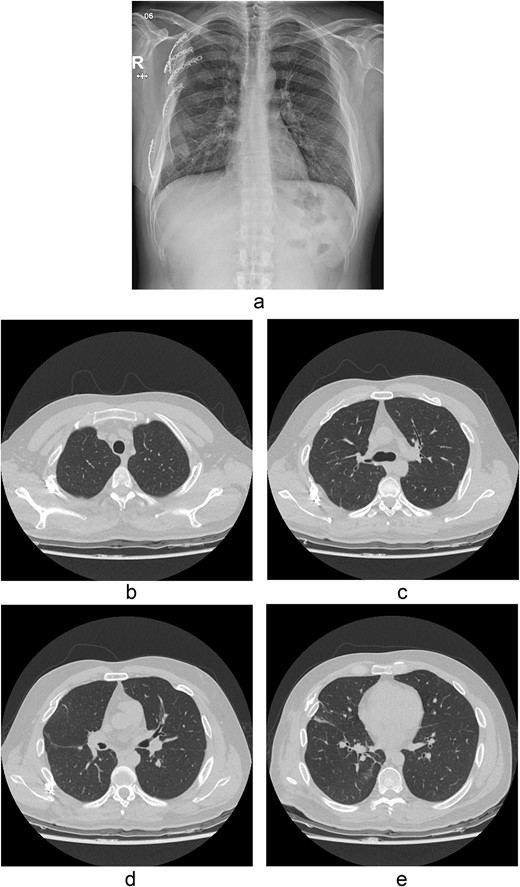

Chest radiograph and CT scan 10 months after the accident. (a) Chest radiograph showed well-healed fractured ribs and expanded lungs without active lesions. (b)–(e) Non-enhanced axial chest CT images showed recovery from injury.